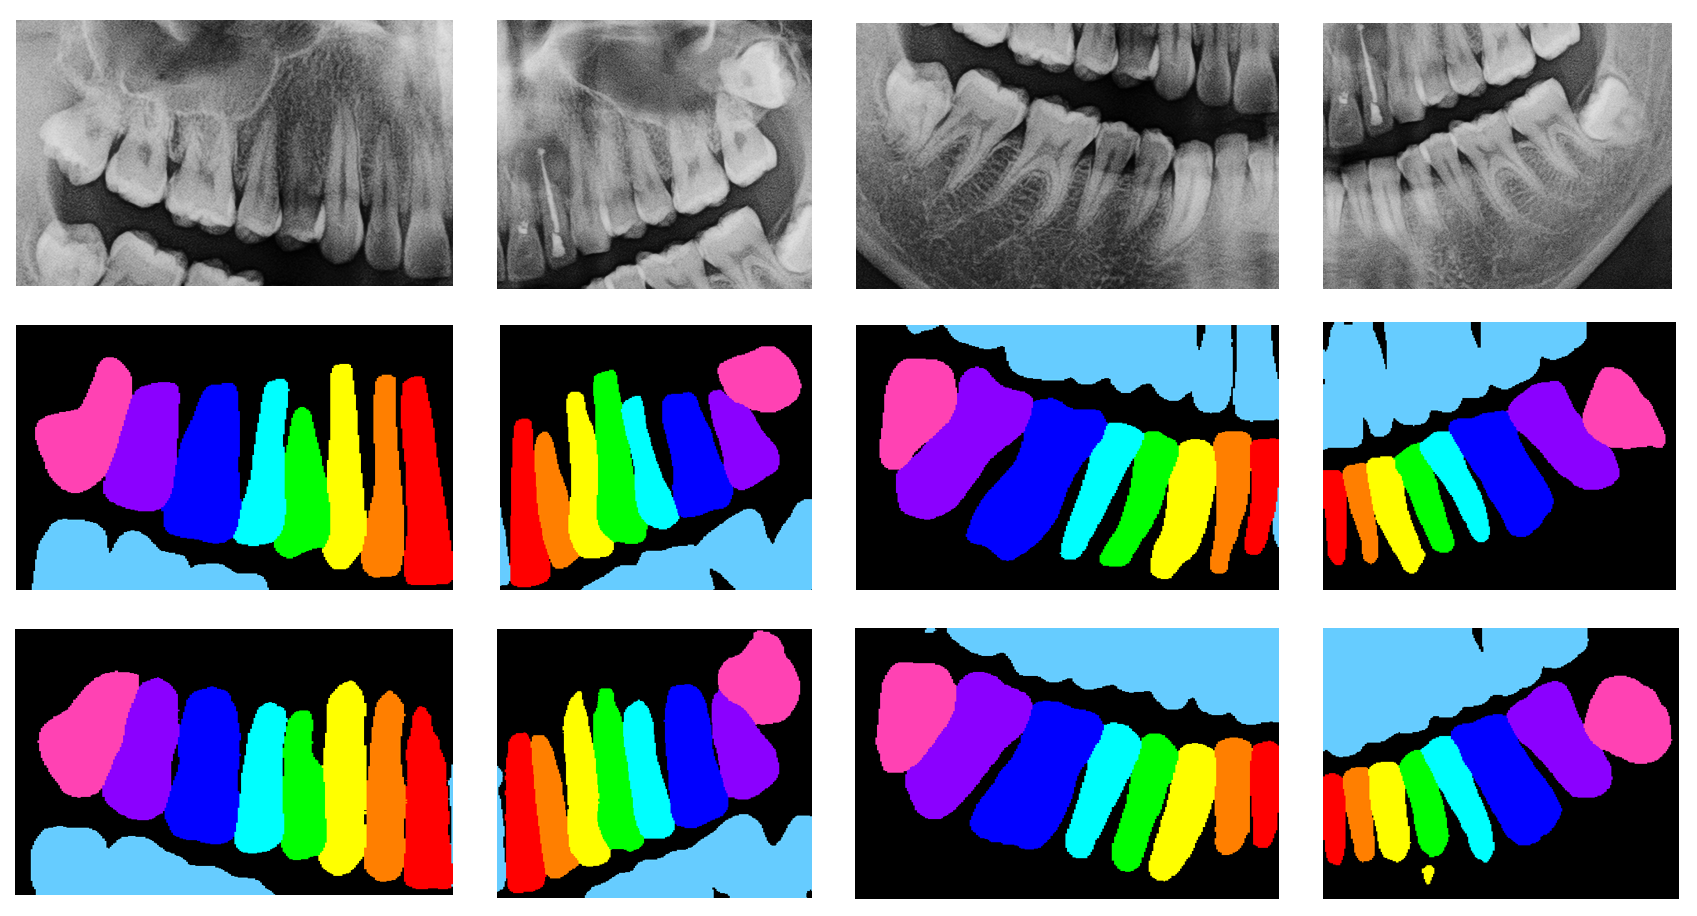

Quantitative results are shown in Fig. 2 3 4.

In Fig. 4, we show the disease detection results of the image, and the final labels after label matching, where the enumeration ids are converted to FDI notation(indexes begin from 0). Here we only draw disease instances whose scores are higher than 0.3. There will be much more instances if lowering the threshold, which may be helpful for getting higher metrics. As shown in these figures, our method can detect diseased teeth, and match their enumeration ids correctly.

Refer to caption

Figure 4: Disease detetcions and final labels